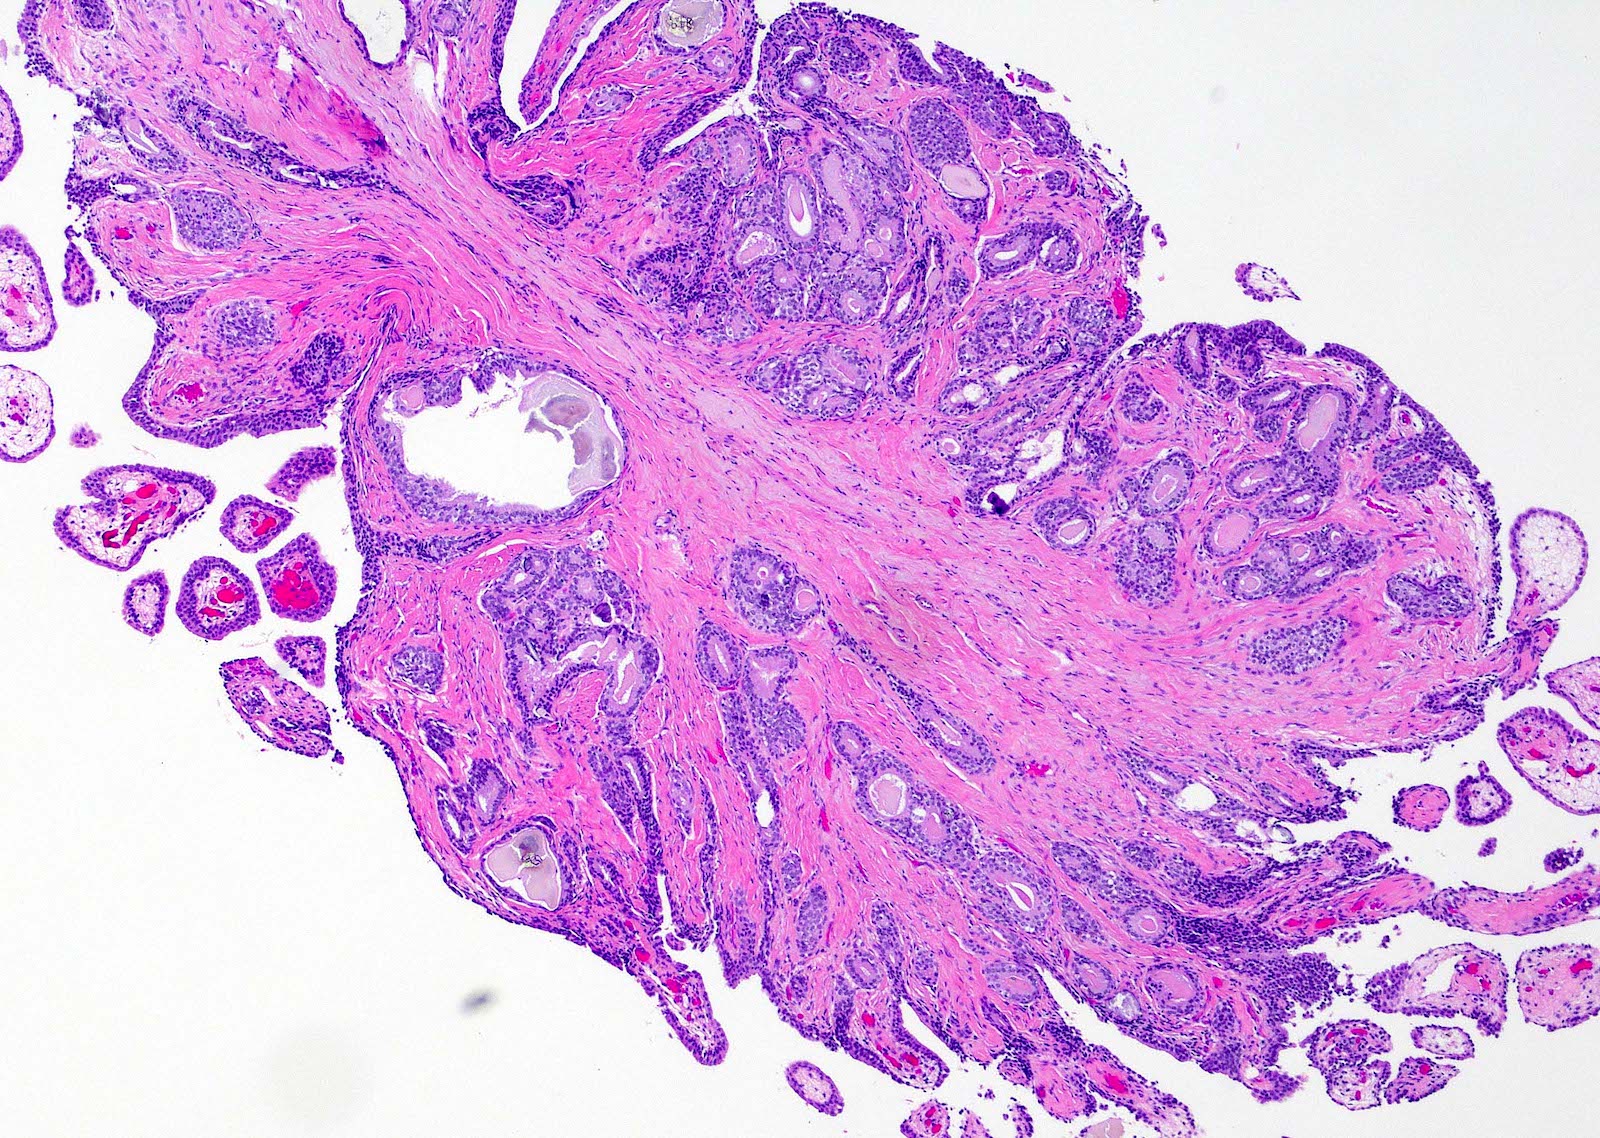

- Fibroepithelial urethral polyp (Am J Surg Pathol 2005;29:460):

- Pattern 1: most common pattern includes the following features

- Broad cloverleaf-like and club-like projections covered by normal urothelium and composed of dense fibrovascular stroma with florid cytitis cystica et glandularis (most common morphologic variant)

- Back to back glands present in the stalk

- Anastomosing nests of benign urothelial cells resembling inverted papilloma

- Dilated cysts with intracystic papillary contents

- Degenerative reactive atypia of stromal cells

Microscopic (histologic) images

Contributed by Y. Albert Yeh, M.D., Ph.D.

Fibroepithelial polyp